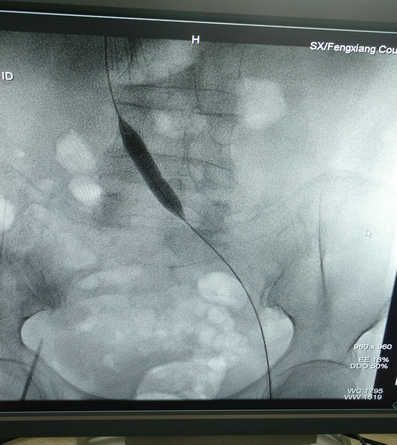

6月30日晚8时,在刘亚民教授的精心指导下,介入科李渊博主治医师与科室医护人员为该患者实施了血管开通、球囊扩张成形及支架置入术,术后造影,左侧髂静脉通畅,患者安全返回病房。

血管开通、球囊扩张成形及支架置入术在我院是第一例,也宝鸡地区县级医院开展的第一例手术,原来只能在三甲医院开展的手术,现在在家门口就能够实施,为广大患者提供了便利、节省了费用,也标志着我院在血管疾病诊治方面又迈出了新的一步。